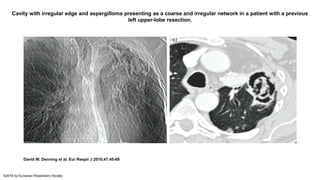

• Prior to aspergilloma formation, a mat of fungal growth on the

appearance of a bumpy or irregular interior cavity appearance.

Cavity with irregular edge and aspergilloma presenting as a coarse and irregular network in a patient with a previous

left upper-lobe resection.

David W. Denning et al. Eur Respir J 2016;47:45-68

©2016 by European Respiratory Society

• Prior toaspergilloma formation, a mat of fungal growth on the interior surface of the cavity is common, with a distinctive appearance of a bumpy or irregular interior cavity appearance.

Cavity with irregularedge and aspergilloma presenting as a coarse and irregular network in a patient with a previous left upper-lobe resection. David W. Denning et al. Eur Respir J 2016;47:45-68 ©2016 by European Respiratory Society

• An aspergillomatypically starts as a surface infection following colonisation in a lung cavity or a bronchiectasis. Aspergilloma is a late manifestation of CPA. • Aspergilloma typically presents as an upper-lobe, solid, round or oval intracavitary mass, partially surrounded by a crescent of air, the “air-crescent” sign, mobile on prone position. • Fungus balls do not enhance after i.v. injection of contrast media.

• #57 Cavity with irregular edge and aspergilloma presenting as a coarse and irregular network in a patient with a previous left upper-lobe resection. Note the apical pleural thickening bordering the cavity well seen on the topogram of the a) computed tomography scan. b) Axial view with lung window at the level of the left upper lobe.